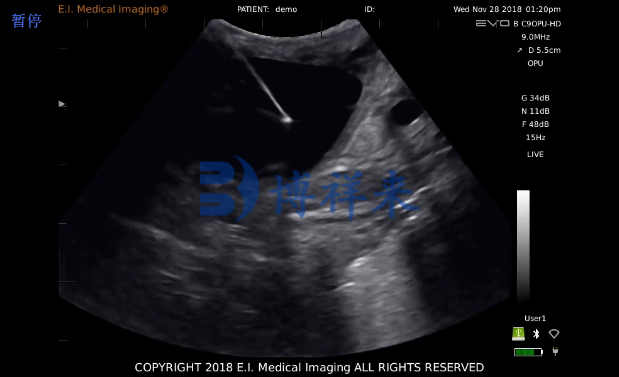

马用活体采卵仪(俗称 OPU 设备)是配套超声探头、穿刺装置和抽吸系统的一体化设备,用于在阴道超声引导下对母马卵巢内卵泡进行经阴道穿刺与液体抽取,从而获得未成熟或成熟卵母细胞,随后在体外进行培养或体外受精/胚胎培养等后续操作。该技术来源于人类与牛的经阴道超声引导取卵,已被移植到马匹繁育实践中,成为一种可重复、微创的取卵手段。

设备精准:现代马用活体采卵仪配合高分辨率超声探头与引导装置,能更准确找准小卵泡,提高取卵率。许多厂商已推出专为牛/马设计的 OPU 探头与抽吸系统。

超声探头分辨率与频率范围:能清晰显示小于 1–4 mm 的卵泡更有利于提高卵子检出率。

推荐我们的活体采卵仪 ,该采卵仪图像清晰度高,采用128阵元高清一体式采卵探头,非常适合牛马采卵用。